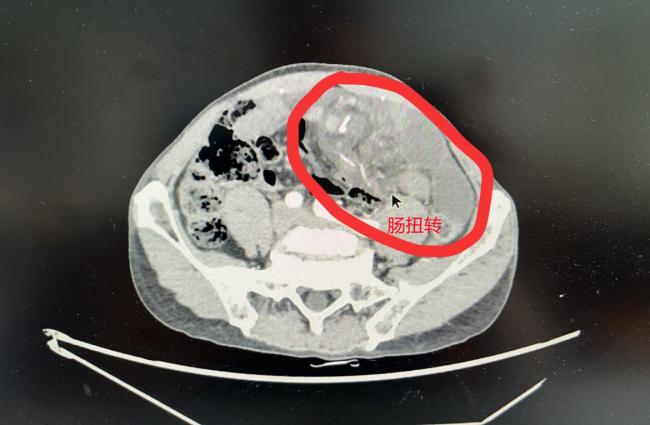

近日,陈大爷腹痛剧烈,被送入医院急诊科,检查发现是肠扭转,近5米小肠广泛缺血、濒临坏死,危及生命,胃肠外科主任许荣华团队两次“开膛破肚”,成功保住了陈大爷的小肠,让其转危为安。

急诊CT影像检查后,陈大爷被诊断为“肠梗阻”,也就是肠道被堵塞了,当场被收入胃肠外科住院治疗。

查阅CT影像,胃肠外科副主任医师刘军辉也吓了一跳:陈大爷的小肠肠管多处严重扩张,且扭曲成团块,肠壁出现了弥漫性水肿,多处渗出。

结合陈大爷的症状,胃肠外科主任许荣华判断:患者是“肠扭转”了,且小肠已广泛缺血,濒临坏死,情况危急。

打开腹腔,里面的情况证实了许荣华的判断:陈大爷腹腔内大面积肠管淤血,暗红色的血性腹水源源不断地涌出,肠子发生扭转,距离十二指肠悬韧带100cm处的有一个粘连带,粘连带形成套索,卡压住剩余小肠肠管和供应小肠血供的血管,有将近5米的肠子因为严重淤血、缺血已经变成暗红色,处于坏死边缘。